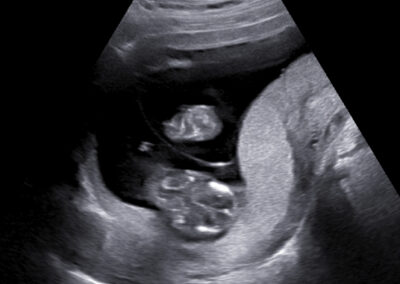

Používáme špičkové přístroje a všichni naši lékaři jsou držiteli certifikátu Fetal Medicine Foundation (FMF) na všechny typy ultrazvukových vyšetření v těhotenství. Při vyšetření miminka se vždy řídíme FMF protokoly, prohlížíme i drobné detaily a ke zpřesnění používáme kombinaci 2D a 3D ultrazvuku. V průběhu vyšetření vám vždy vysvětlujeme, co právě vyšetřujeme a co s námi můžete vidět na monitoru. Po skončení vyšetření vám srozumitelně vysvětlíme výsledky (a případně závažnost situace) a navrhneme další postup.

Vyšetření časného těhotenství NT screening Downova syndromu v 1.trimestru Screening vrozených vad ve 2. trimestru Screening ve 3. trimestru